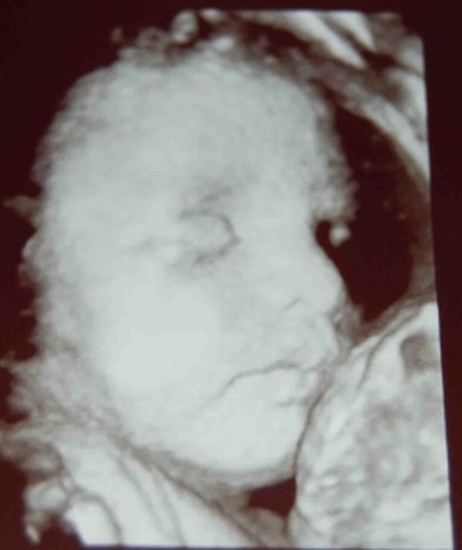

Edina! Nagyon szépa pici fiad!